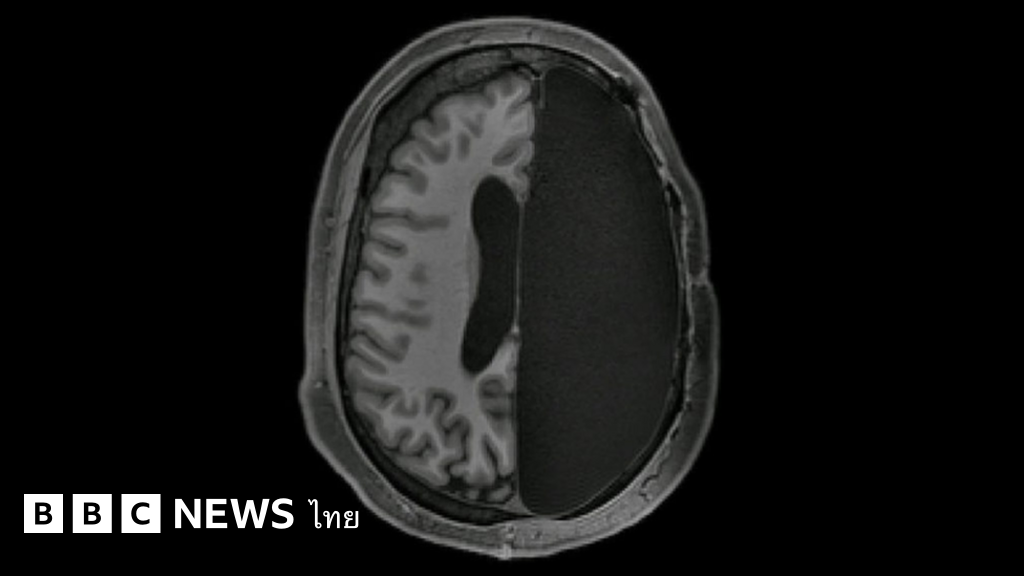

สมองที่เหลือแค่ครึ่งซีก ทำงานเชื่อมโยงกันได้แข็งแกร่งยิ่งกว่าสมองปกติ

แต่อย่างไรก็ตาม ผลการศึกษาล่าสุดกลับพบความมหัศจรรย์ของสมองมนุษย์ที่พิสูจน์แล้วว่า แม้เนื้อสมองจะเหลืออยู่เพียงครึ่งเดียว แต่มันสามารถจะปรับตัวให้ทำงานเชื่อมโยงกันได้อย่างแข็งแกร่งขึ้น เพื่อชดเชยส่วนที่ขาดหายไป และดูเหมือนว่าจะทำงานได้อย่างแข็งขัน ยิ่งกว่าสมองที่เป็นปกติของคนทั่วไปด้วยซ้ำ

ทีมผู้วิจัยสันนิษฐานว่า การปรับตัวของสมองส่วนที่เหลืออยู่ของคนไข้เหล่านี้ น่าจะมีความเกี่ยวข้องกับเรื่องน่าประหลาดใจดังกล่าว จึงมีการทดลองให้ผู้ที่เคยผ่านการผ่าตัดเอาเนื้อสมองออกซีกหนึ่งในวัยเด็ก 6 ราย เข้ารับการตรวจสมองด้วยเครื่องสแกน MRI และเปรียบเทียบข้อมูลที่ได้กับกลุ่มควบคุมซึ่งมีสมองสมบูรณ์ตามปกติ รวมทั้งเปรียบเทียบกับฐานข้อมูลผลสแกนสมองของชาวอเมริกัน 1,482 คนด้วย

ผลปรากฏว่าในภาวะที่ร่างกายกำลังพักผ่อน สมองครึ่งซีกกลับมีการทำงานตอบสนองเชื่อมโยงกันระหว่างเครือข่ายเซลล์ประสาท 7 กลุ่ม อย่างแข็งขันและแข็งแกร่งเกินคาด โดยมีการแลกเปลี่ยนข้อมูลระหว่างเครือข่ายเซลล์ประสาทที่ทำหน้าที่ต่าง ๆ มากขึ้นกว่าคนทั่วไป ไม่ว่าจะเป็นเครือข่ายการรับรู้ประสาทสัมผัส การควบคุมอารมณ์ การใช้ความทรงจำและสมาธิ ซึ่งโดยปกติแล้วจะต้องใช้การทำงานประสานกันระหว่างสมองสองซีก